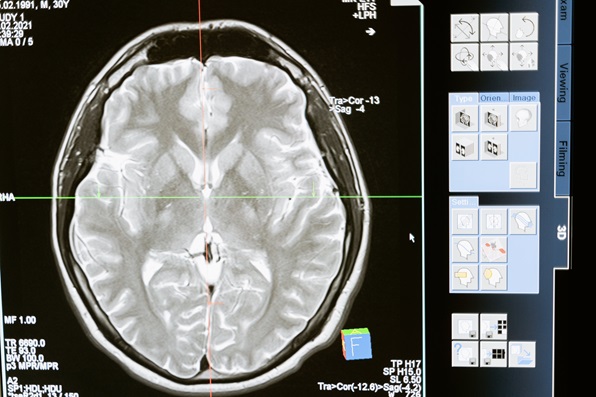

보건소에 방문하시면 아래와 같이 검사과정을 거치게 됩니다. 1단계 인지선별검사에서 저하된 걸로 나오면 2단계 진단검사를 받게 되는데, 전문의 진료와 신경심리검사, 일상생활 척도검사 등을 진행하게 됩니다. 진단검사에서도 치매의심이 나오게 되면 3단계 감별검사를 받도록 권유합니다. 혈액 검사, 요검사, 뇌 영상 촬영 등을 통해 보다 확실하게 진단할 수 있는 검사입니다.

| 3단계 | 감별검사(혈액 검사, 요검사, 뇌 영상 촬영 등) | 지자체 협약병원 | 지차체마다 소득기준에 따라 검사비용이 상이함 |